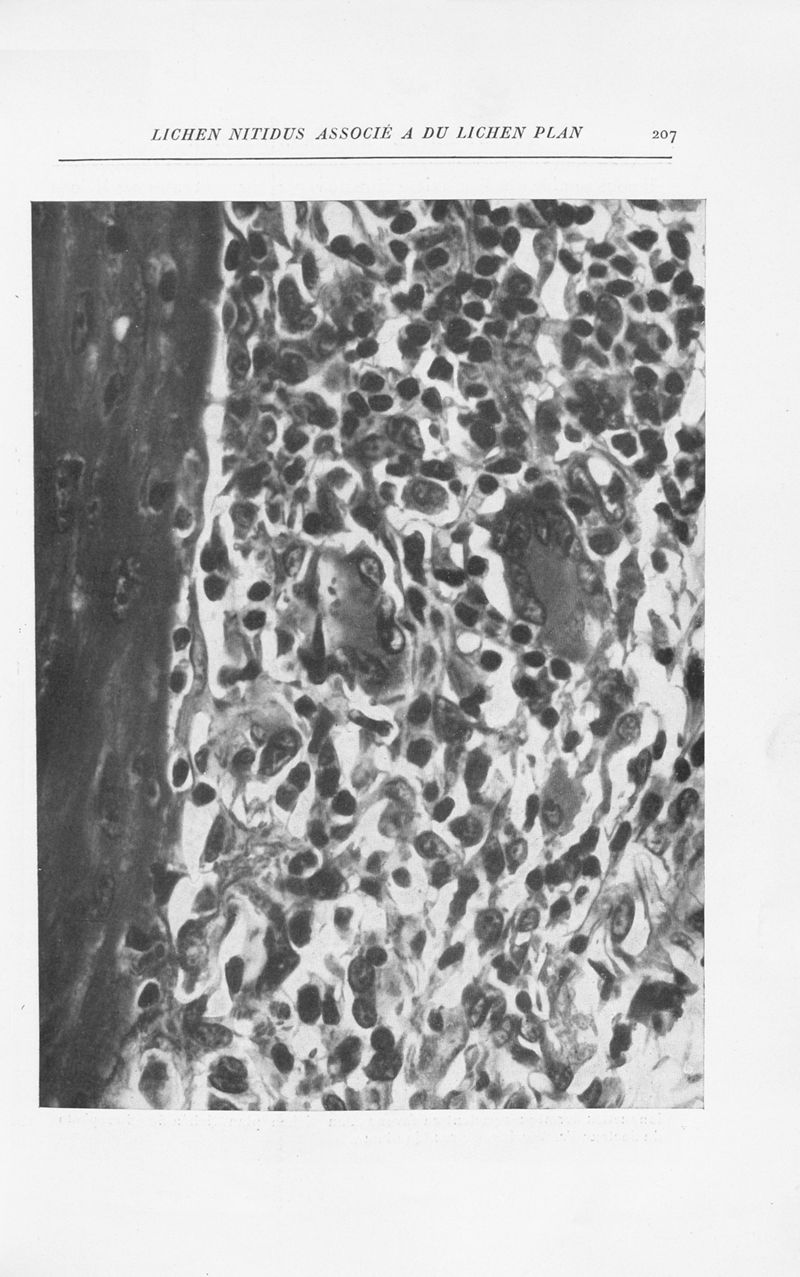

Annales de dermatologie et de syphiligraphie

7ème série, tome VIII. - Paris : Masson, 1937.